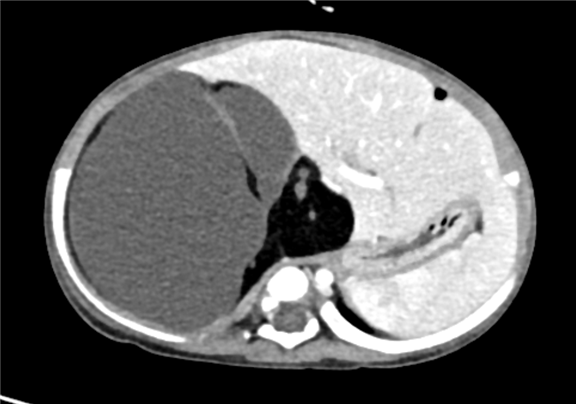

上腹部增强CT:腹膜后巨大混杂密度肿块影,考虑畸胎瘤可能性较大

术前CT检查:

动脉期

静脉期